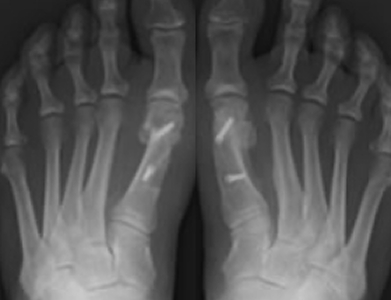

An exostectomy is the surgery to remove the bony bump that defines the bunion. This surgery is often just one part of the bunion surgery and is paired with soft tissue procedures and a technique to straighten the toe and support joint health. Removing the bunion lump alone will not solve the problem. As you can see from x-rays, bunions include significant shifts in how the toe bone lies. To fully solve a bunion, other steps must be taken to straighten the toe.